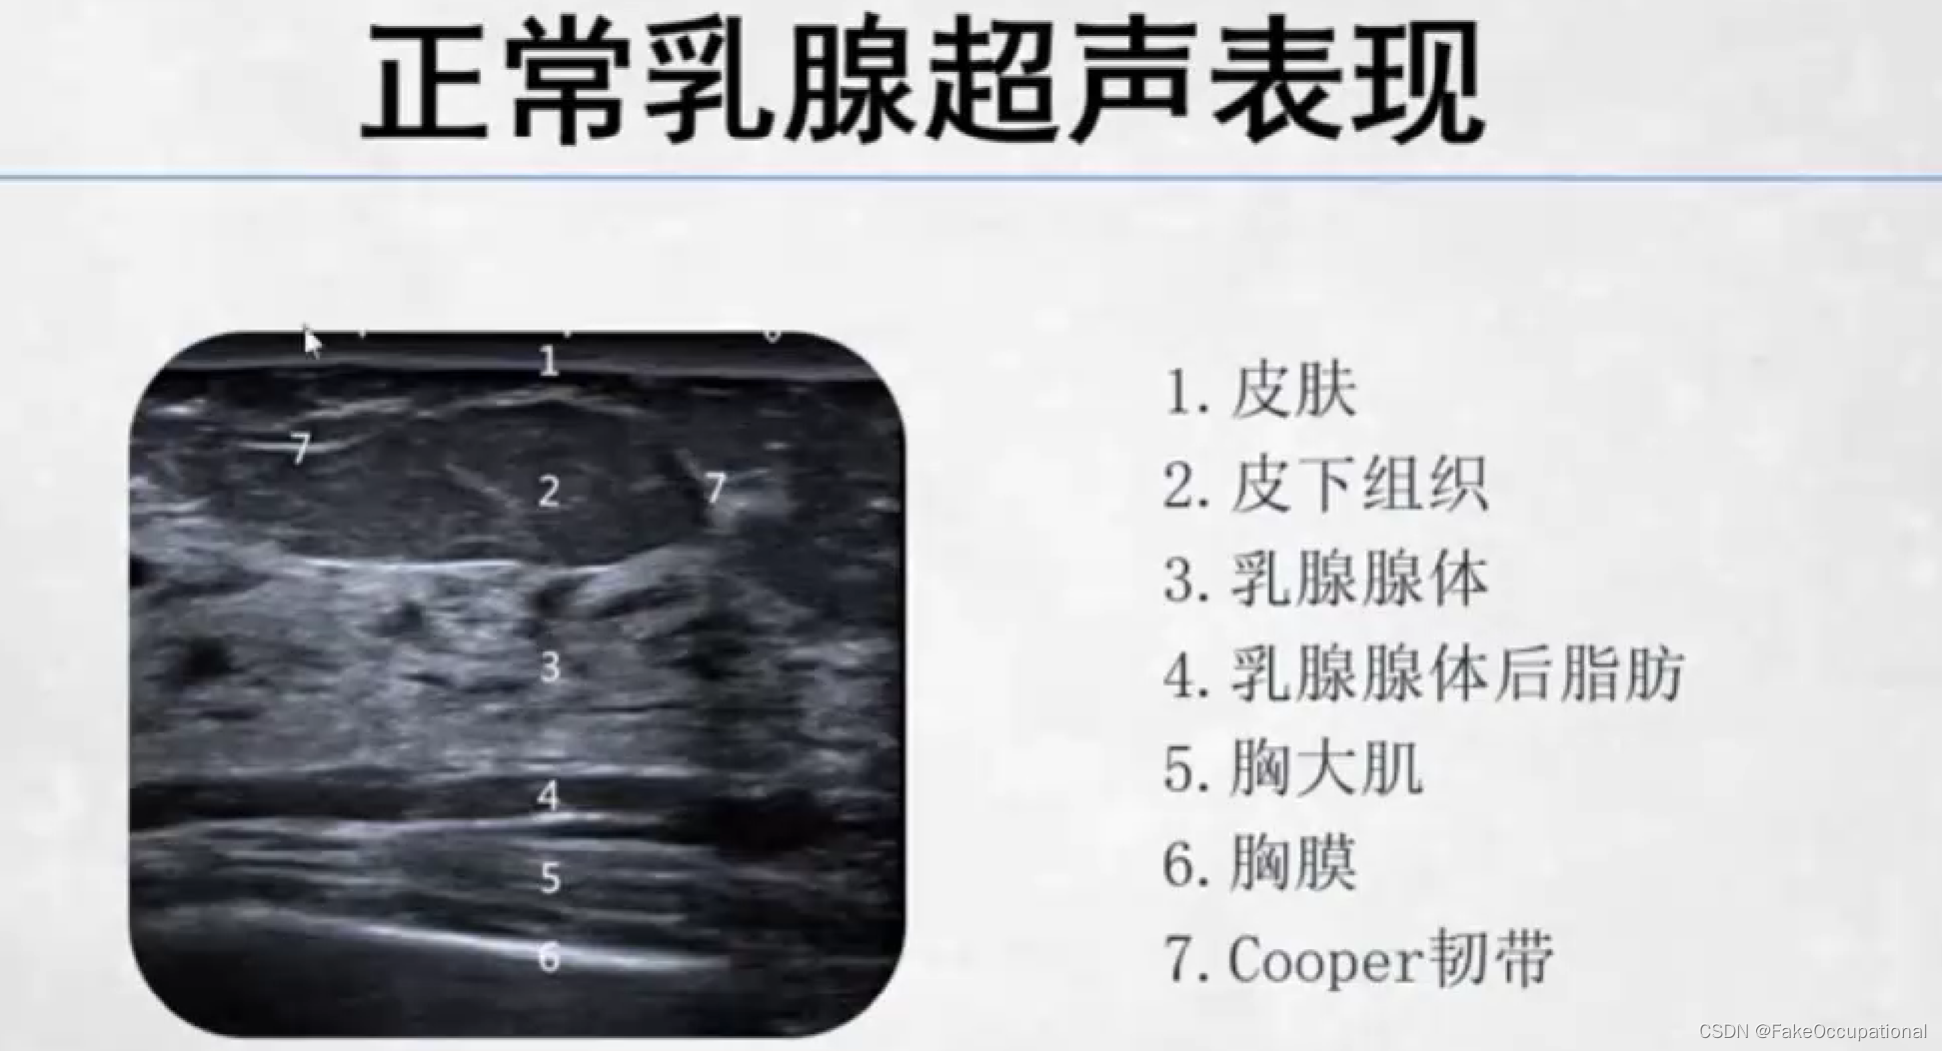

正常乳腺超声表现

- 高回声的皮肤层,低回声的皮下脂肪层